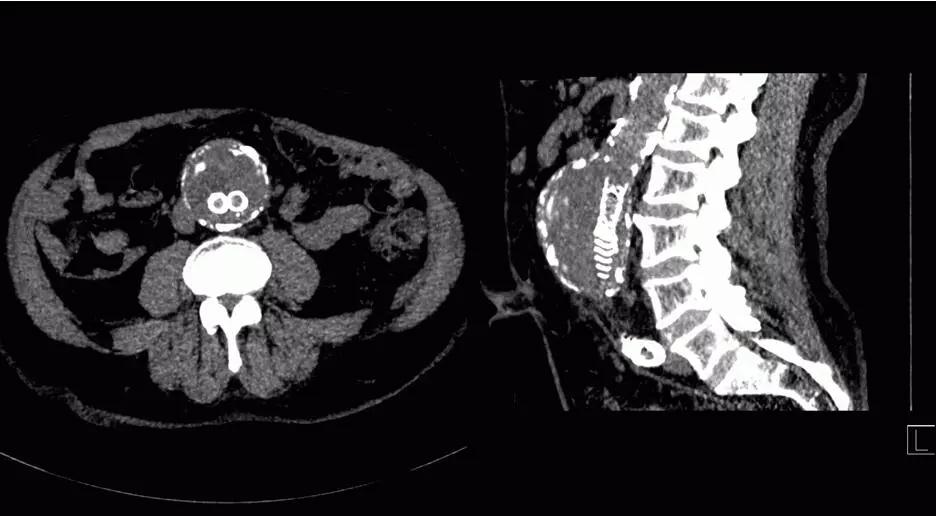

傳統(tǒng)DSA成像有創(chuàng)而且操作復(fù)雜、掃描范圍受限。

SOMATOM Force 突破技術(shù)界限,將血流評(píng)估覆蓋范圍擴(kuò)大至80cm,特別適合大范圍下肢血管疾病診斷,一次掃描一次注射即可無創(chuàng)精確判斷病變,更加精確地制定臨床決策,選擇合理的治療方法。

△80厘米無創(chuàng)CT DSA,影像決策診療